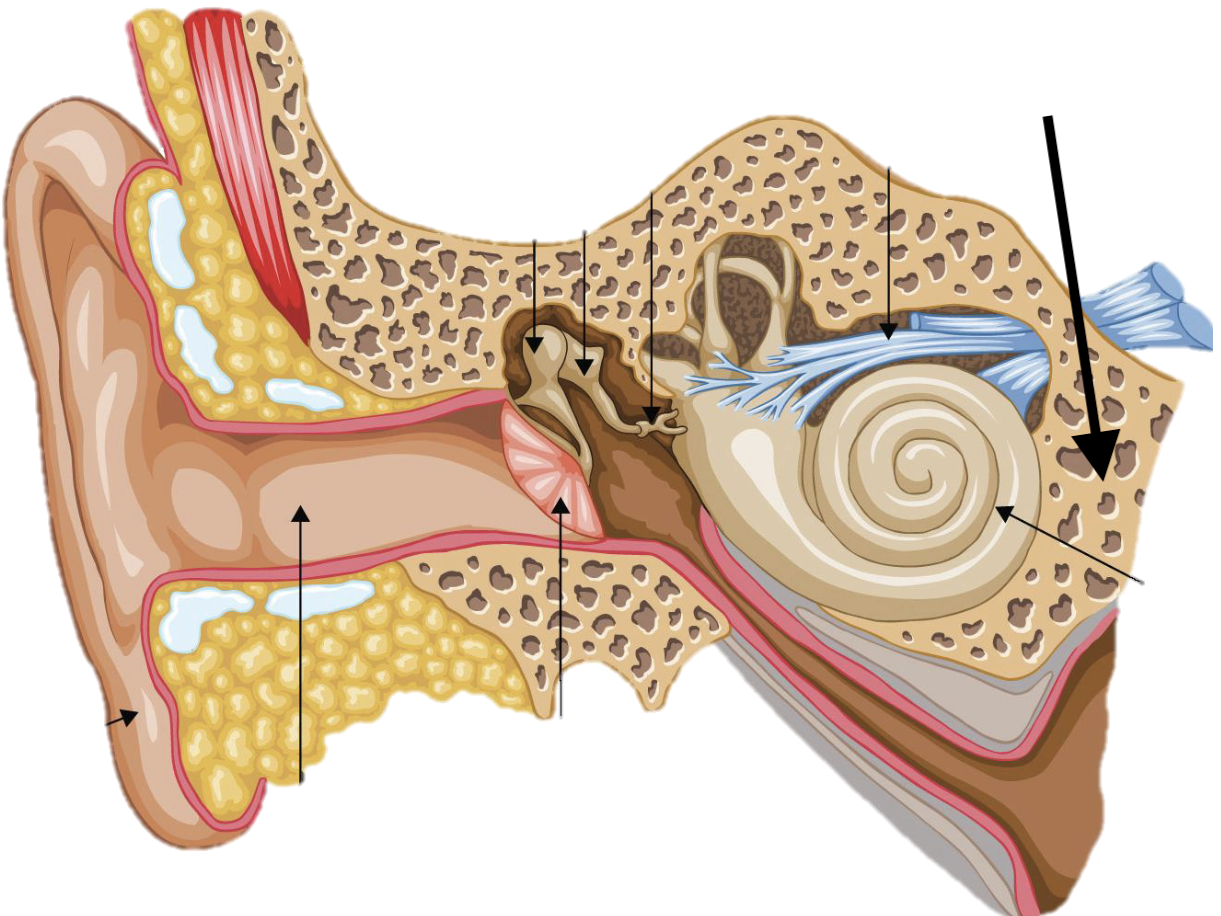

What bone markings are on the ANTERIOR temporal bone?

External acoustic meatus, zygomatic arch, mandibular fossa

What bone markings are on the POSTERIOR temporal bone?

Internal acoustic meatus, petrous portion, carotid canal

Name the feature of the ear ossicle

External acoustic meatus

Name the feature of the ear ossicle

Malleus

Name the feature of the ear ossicle

Incus

Name the feature of the ear ossicle

Stapes

Name the feature of the ear ossicle

Internal acoustic meatus

Name the feature of the ear ossicle

Cochlea

Name the feature of the ear ossicle

Temporal bone